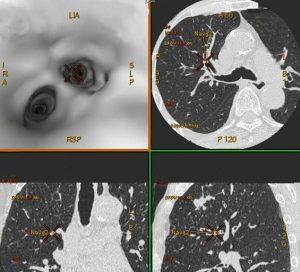

この検査は気管支内視鏡の菅を病巣まで進め、先端の穴から鉗子を伸ばして組織片を採取する方法です。 しかし菅を進める肺野内の気管支はとても複雑な形態で、目的の病巣へたどり着くためにはいくつもの分岐を正しい方向へ進まなければ到達できません。より短時間で正確に気管支内視鏡を目的病巣に進めるために、この検査前に胸部CT検査を行い、気管支の詳細な三次元画像を構築し、病巣までの経路を事前にシミュレーションしています。検査実施医は検査前にこの三次元画像で作成した道案内画像を見てルートを学習し、確実・迅速に「経気管支肺生検」を行っています。